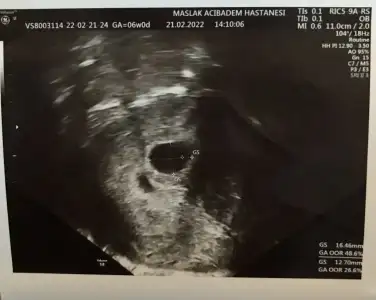

Kızlarrrr bu da benim minnoşum ❤️

Bu arada transfer tarihine göre 6+0 mışım nedense yanlış hesaplamışım 😀